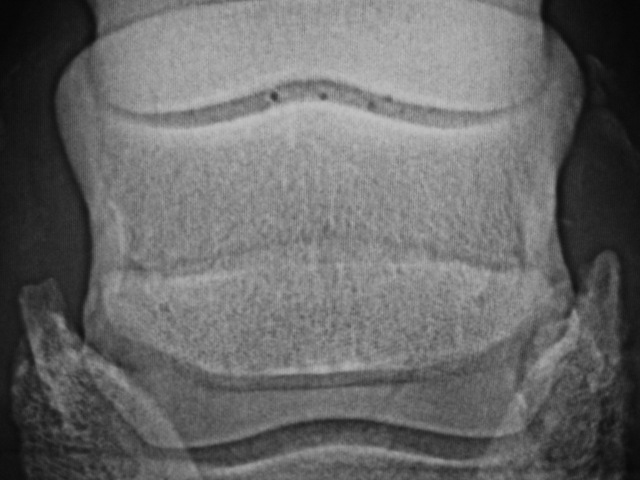

Dies ist das Bild eines Strahlbeines ganz ohne Kanäle, wie man es eher selten sieht. Die Knochenstruktur ist gleichmäßig, die Kontur leicht konvex.